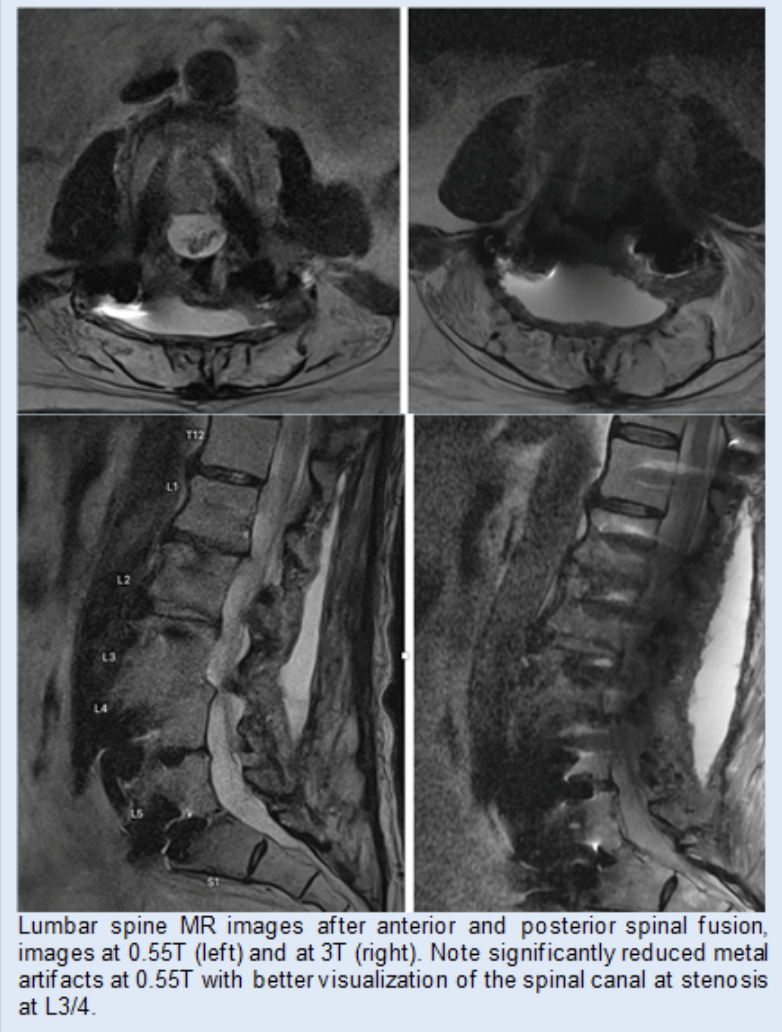

Comparison of lumbar spine MRI images after anterior and posterior spinal fusion acquired at 0.55T and 3T, showing reduced metal artifact at lower field strength and improved visualization of the spinal canal at the L3 L4 level.

Using a novel 0.55T system we studied patients with metal implants at the spine (spinal fusion with metal hardware) and hip (hip arthroplasties) and found that imaging at 0.55T had superior image quality and showed abnormalities better than imaging at 1.5 or 3T. We also performed a biophantom study using metallic implants (steel and titanium screws) in pig knees which demonstrated substantial reduction of artifact size resulting in superior depiction of anatomical structures at 0.55 T MRI.